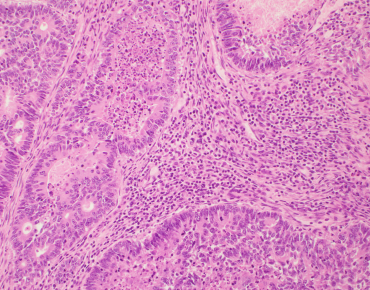

TRAIN YOURSELF

Incorporation of TILs in the Residual Cancer Burden Index

Artifical Intelligence / Deep Learning / Machine Learning approaches to TIL-assessment